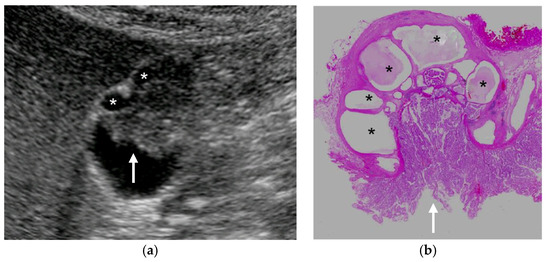

Figure 8. GBC concomitant with localized ADM. (a) US showed a papillary GPL (arrow) with dilated cystic lesions in the fundus. (b) Histopathologically, a papillary GBC (arrow) arose in the surface mucosa of localized ADM and cystic lesions were corresponding to dilated RASs (*: dilated RAS). Reprinted with permission from ref. [7]. Copyright 2021 Japan Society of Ultrasonics in Medicine.